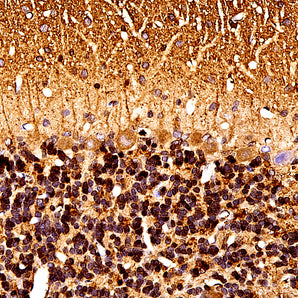

Cell Type Marker